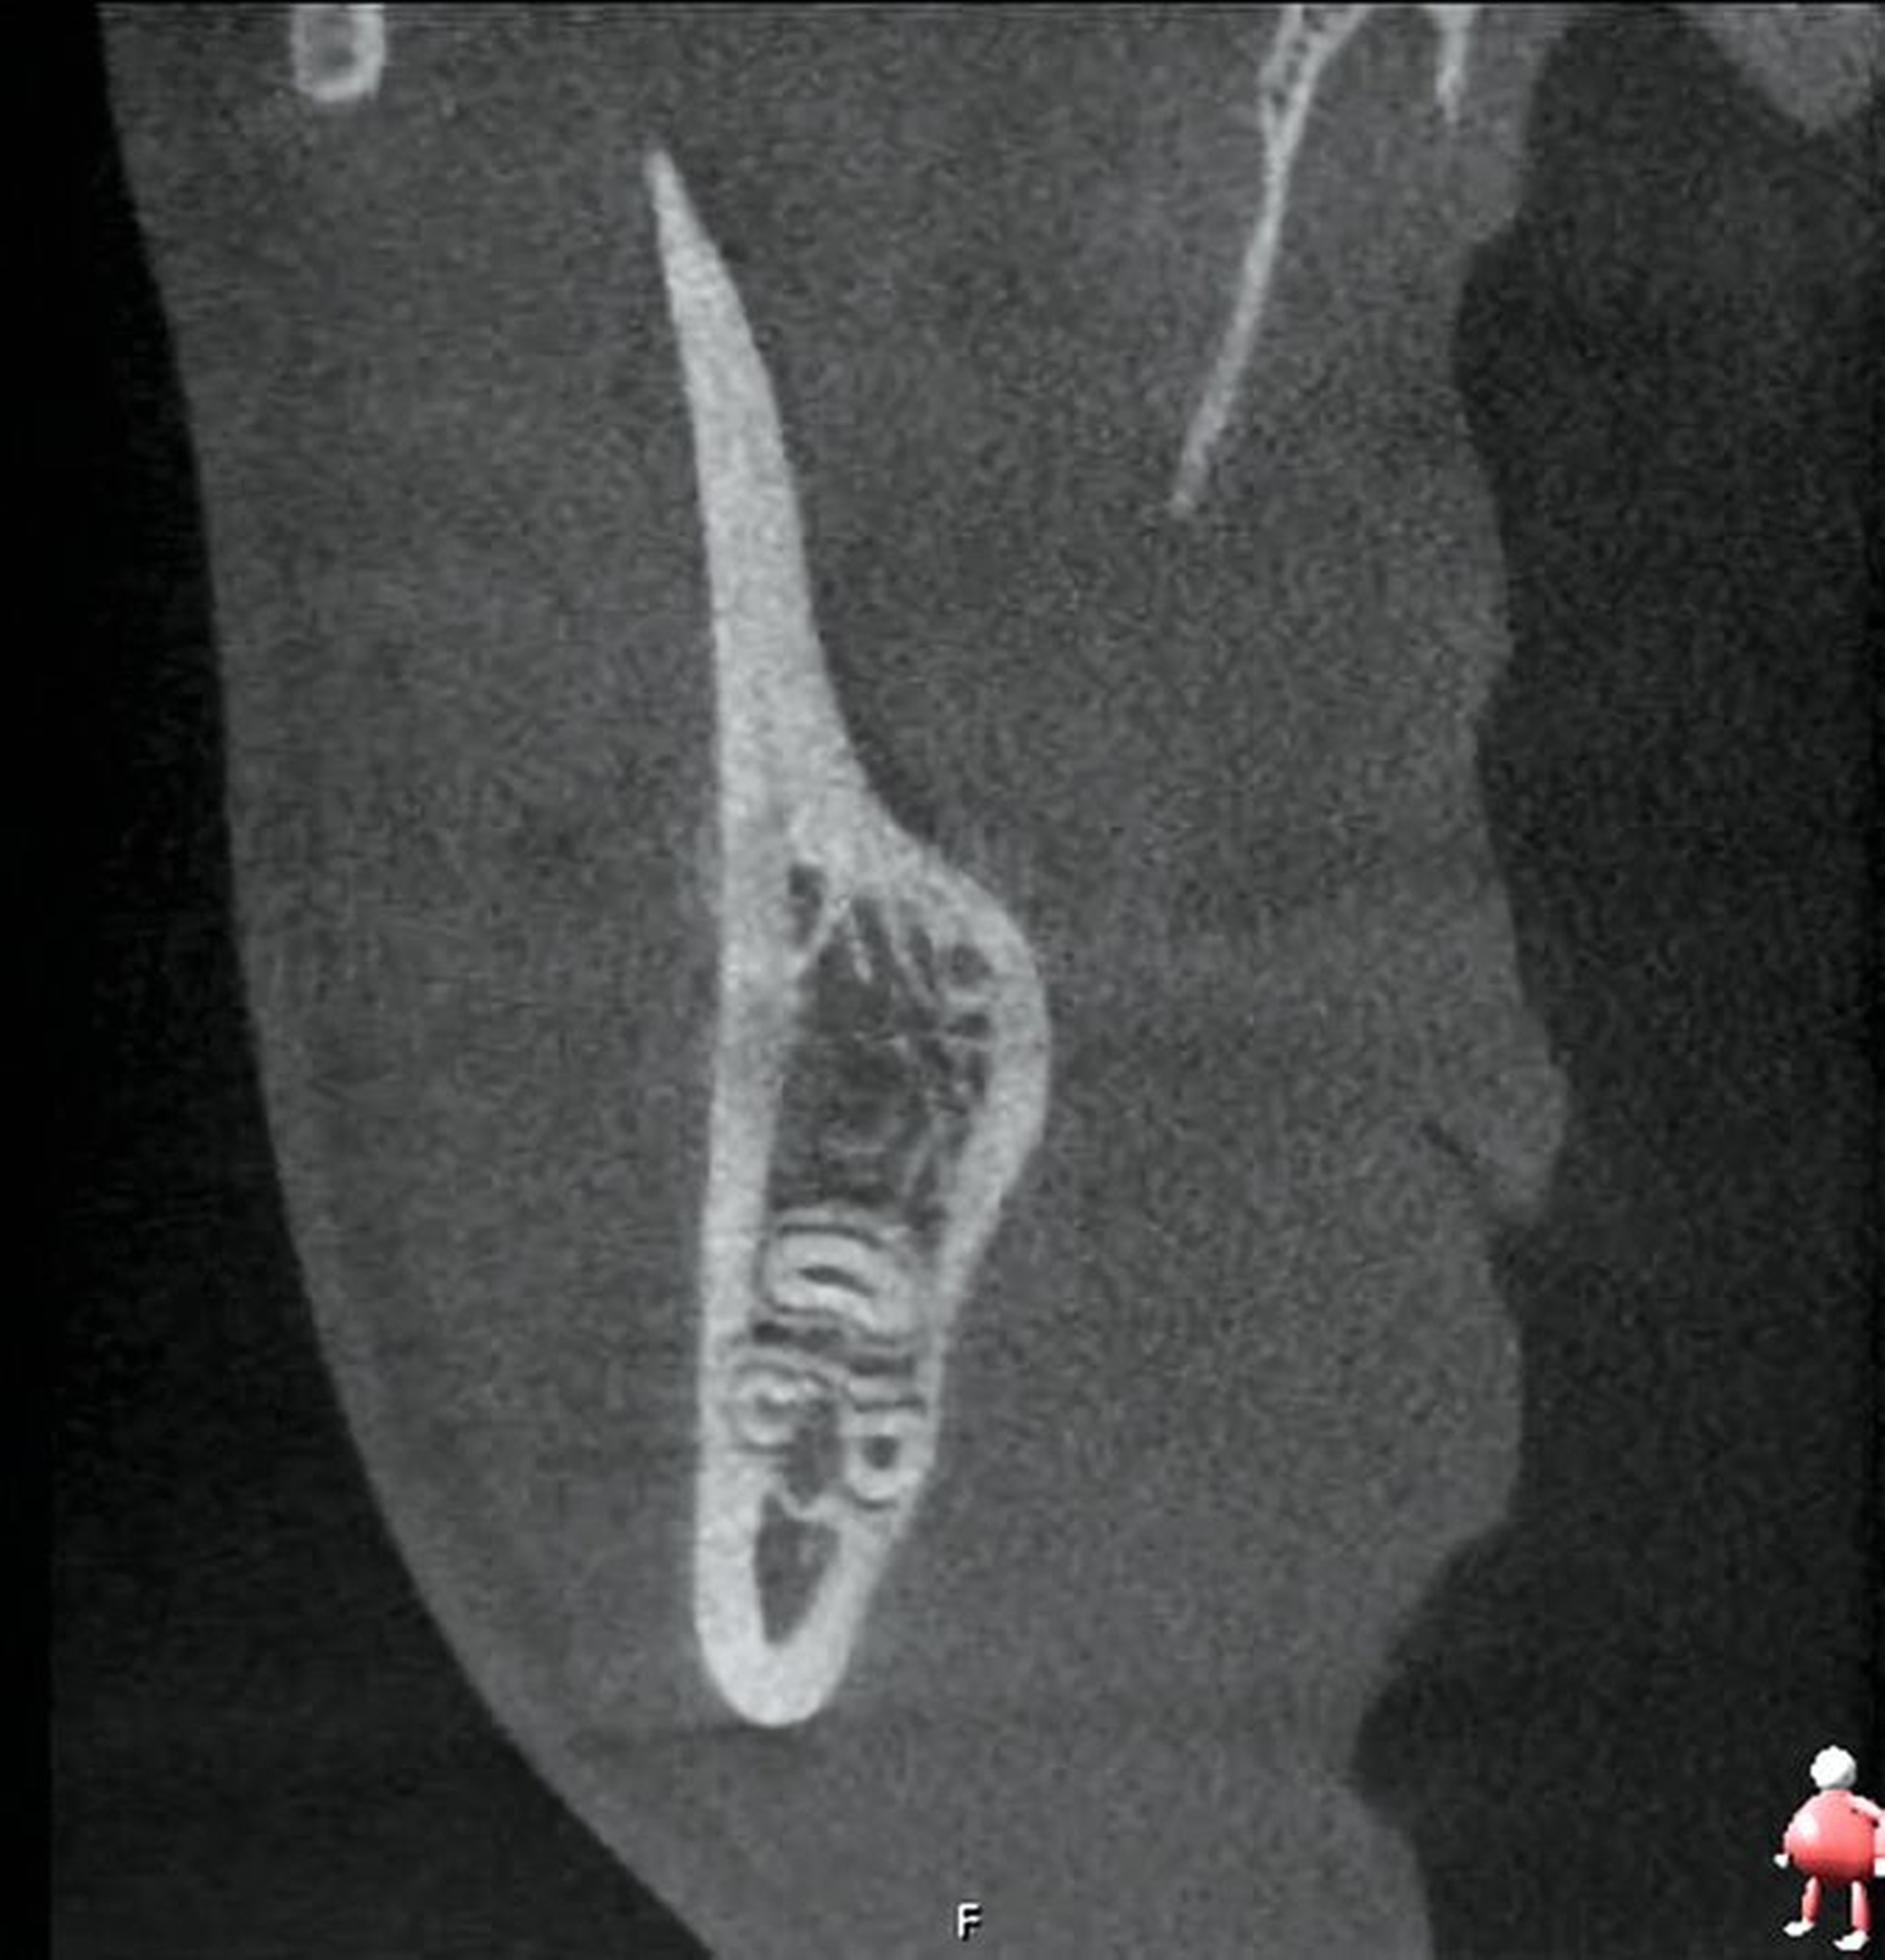

Im Oberkiefer zeigte sich auf der linken Seite neben dem hoch verlagerten und retinierten Zahn 28 ein ebenfalls hoch verlagerter und retinierter Zahn 29 (Abbildung 4) mit enger Lagebeziehung zur Kieferhöhle. Im rechten Oberkiefer erkennt man neben dem hoch verlagerten und retinierten Zahn 18 eine Doppelanlage des Zahnes 19 ebenso in enger Lagebeziehung zur Kieferhöhle (Abbildung 5).